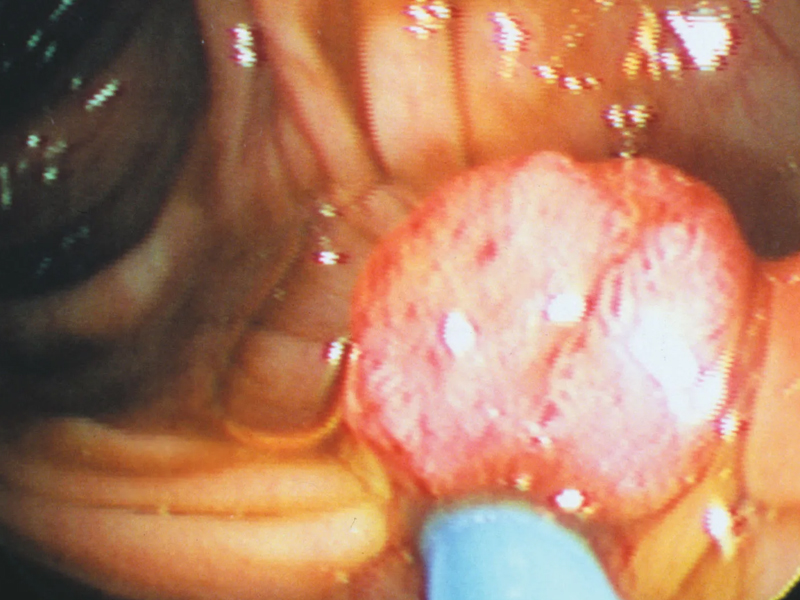

一名 50 歲的台灣女子在沒有吸煙、飲酒及慢性病和家族病史的情況下,卻被診斷出胰臟癌晚期,這一案例引起了醫學界的關注。根據禾馨民權健康管理診所院長林相宏的分享,這名女子在最近一個月感到上腹部不適並迅速減重 9 公斤,最初以為只是胃部問題,然而進一步檢查後發現胰臟有 4 厘米的腫瘤,懷疑為胰臟癌。

林相宏指出,這名女子的腫瘤指數 CA19-9 達到正常值的七倍,顯示腫瘤已經相當嚴重。由於腫瘤的大小及其位置靠近血管,醫生決定先進行化療以縮小腫瘤,然後再考慮手術。林醫生認為,這名女子的腫瘤可能在一年前就已經開始發展,但因為當時只接受了基本的健康檢查,未能及時發現。

儘管這名女子沒有傳統的風險因素,林醫生認為她的缺乏運動及過量攝取人工加工食品和紅肉可能是導致胰臟癌的原因之一。這一觀點強調了生活方式在癌症發展中的潛在影響。